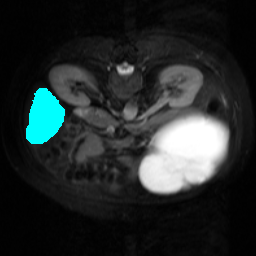

Support

Label

Proposed

In order to assess the performance of the proposed method, we compare the performance of the proposed model with excellent models in recent years. Table 1 and Table 2 shows the comparison results of different models in setting1, while Table 3 and Table 4 shows the comparison results of different models in setting2 on the data set in recent years. PANet[25] is the most widely influential few-shot model in the field of few-shot image segmentation on natural images. SENet [18] is the first few-shot segmentation model proposed for medical images. SSL-ALPNet[19] introduced the milestone of using superpixel self-supervision to train few-shot medical image models. RPNet[29] is a supervised method with a recursive mask optimization module to iteratively optimize the segmentation mask, [27] adapt it into the same self-supervision learning framework and applies setting1 to it and denoted as SSL-RPNet; CRAPNet[27] is the latest SOTA model for 2023. Compared with CRAPNet, our method outperforms most of the state-of-the-art models and only slightly outperforms CRAPNet. Figures 3 and 4 show examples of the model’s segmentation predictions on different datasets, respectively; The first row is the support map, the second row is the label map, and the third row is the segmentation prediction of the model.